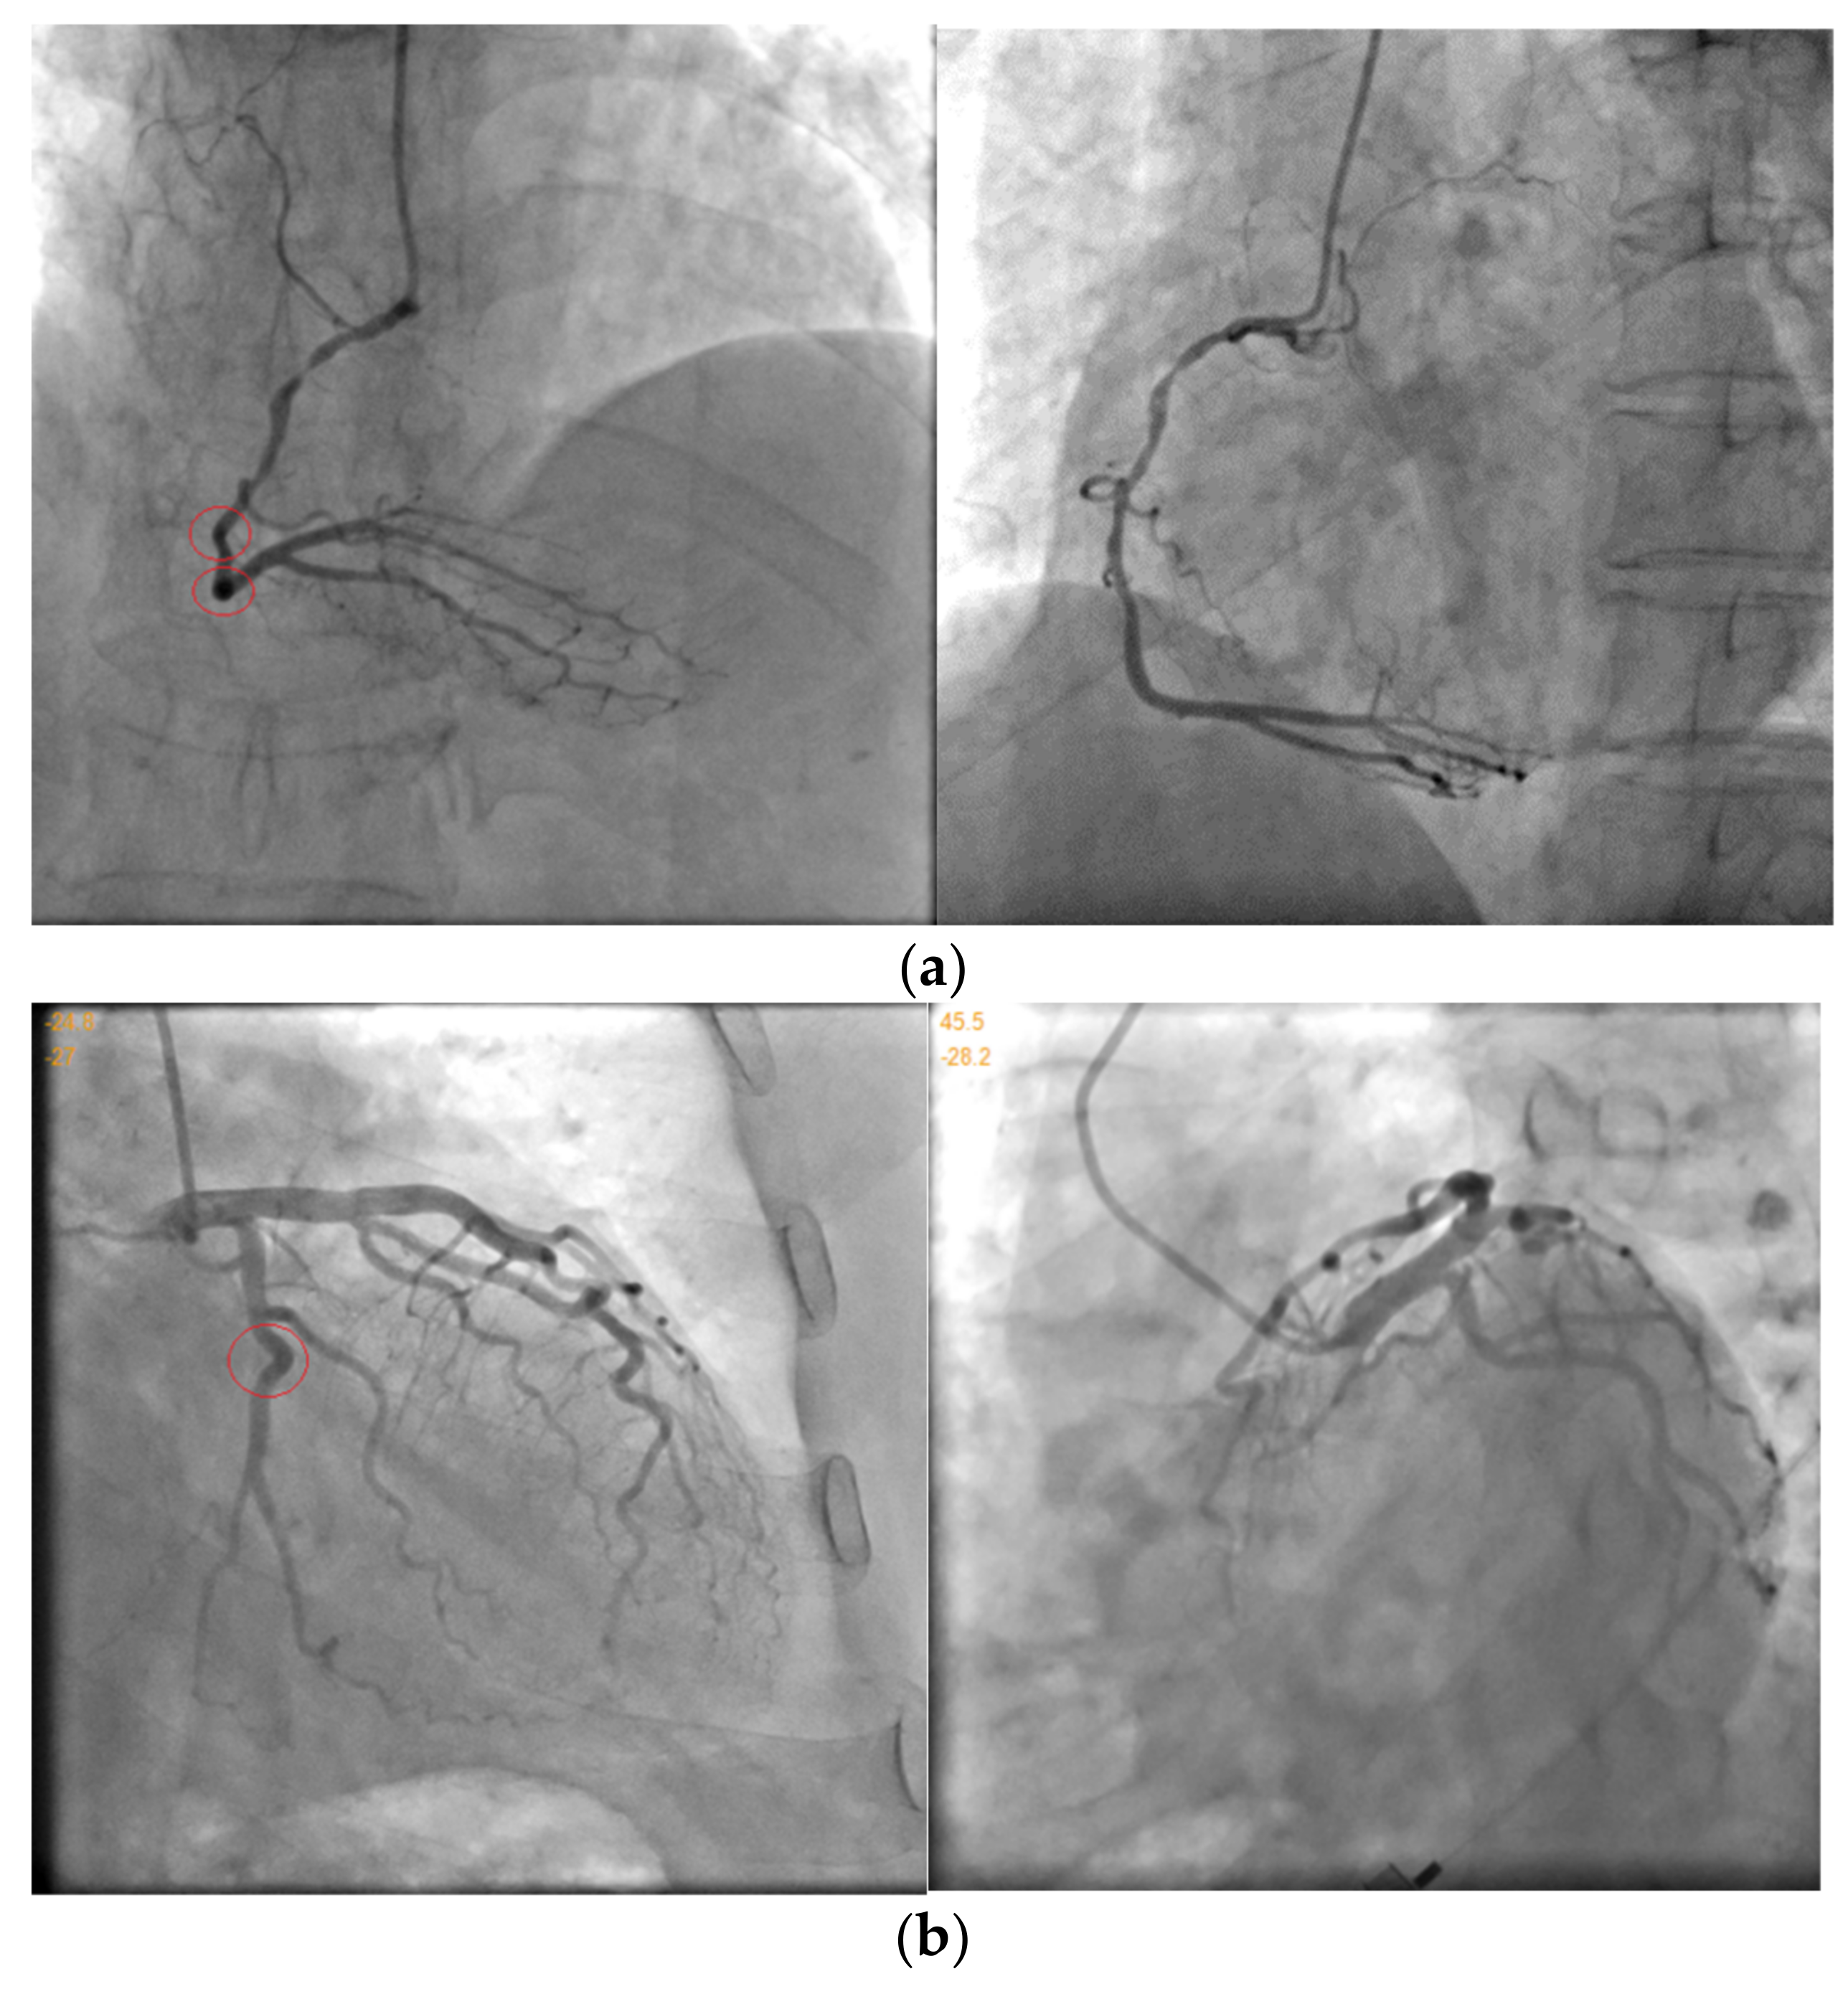

| Data.1 | (a) | 45.5 | −28.2 | 1200 | 749 |

| (b) | −24.8 | −27 | 1147 | 844 | |